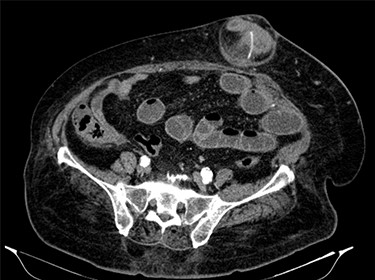

Fluid resuscitation measures, monitoring of urine output and pain control were initiated. Analytically, she had leukocytosis of 227 000/μl with neutrophilia 89%, elevated C-reactive protein 27.1 mg/dl and acute kidney injury with creatinine 1.8 mg/dl and urea 96 mg/dl. Arterial blood gas analysis showed no acidosis, respiratory failure or hyperlactatemia. The computed tomography (CT) scan identified an umbilical hernia containing a small bowel loop, evidenced densification of the hernia fat and some bubbles of extraluminal gas were also present (Fig. 2). An image of high-density and filiform morphology compatible with an FB (Fig. 3) was also identified. Images were consistent with dilation of the proximal intestinal loops, which suggested bowel occlusion.

Abdominal CT: hernia content composed of intestinal loop and densification of the mesentery with gas bubbles.